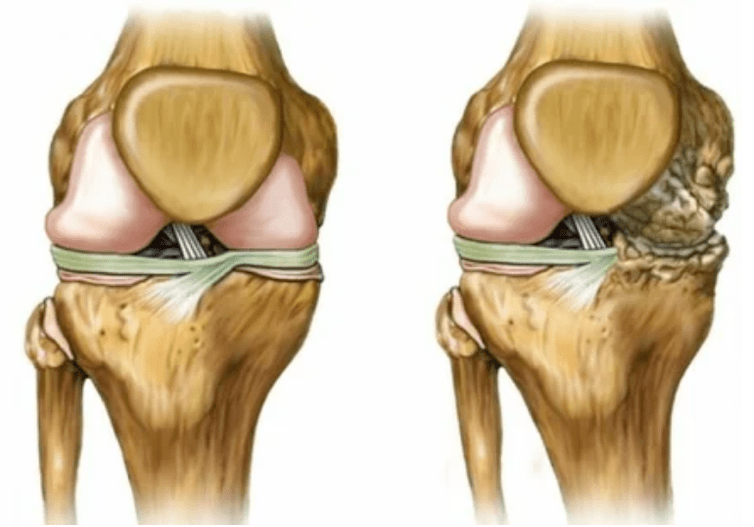

- 3 graos. A miúdo hai dor, é difícil mover a extremidade debido aos cambios na articulación. As lesións son extensas e son notables para o aspecto espido. A deformación da posición conxunta prodúcese, a zona afectada incha e queda vermella. O eixe das extremidades está perturbado, o que leva á complexidade do movemento. Os ligamentos producen cambios patolóxicos. Aparecen subluídos e contracturas. Os músculos adxacentes están reducidos ou estirados a partir da cal se debilita a función contráctil.

Extremidades limitadas. Se aparece nunha forma descoidada da enfermidade, a destrución completa do tecido cartilaxe e a aparición de osteófitos indican. Neste estado, a presión aumenta nas articulacións na parte superior e inferior, desde a que a curvatura pode afectar a ligazón enteira.

- A articulación está completamente destruída;

- A extremidade está inmobilizada, todos os movementos son extremadamente difíciles;

- Forte deformación da articulación ou da extremidade enteira.